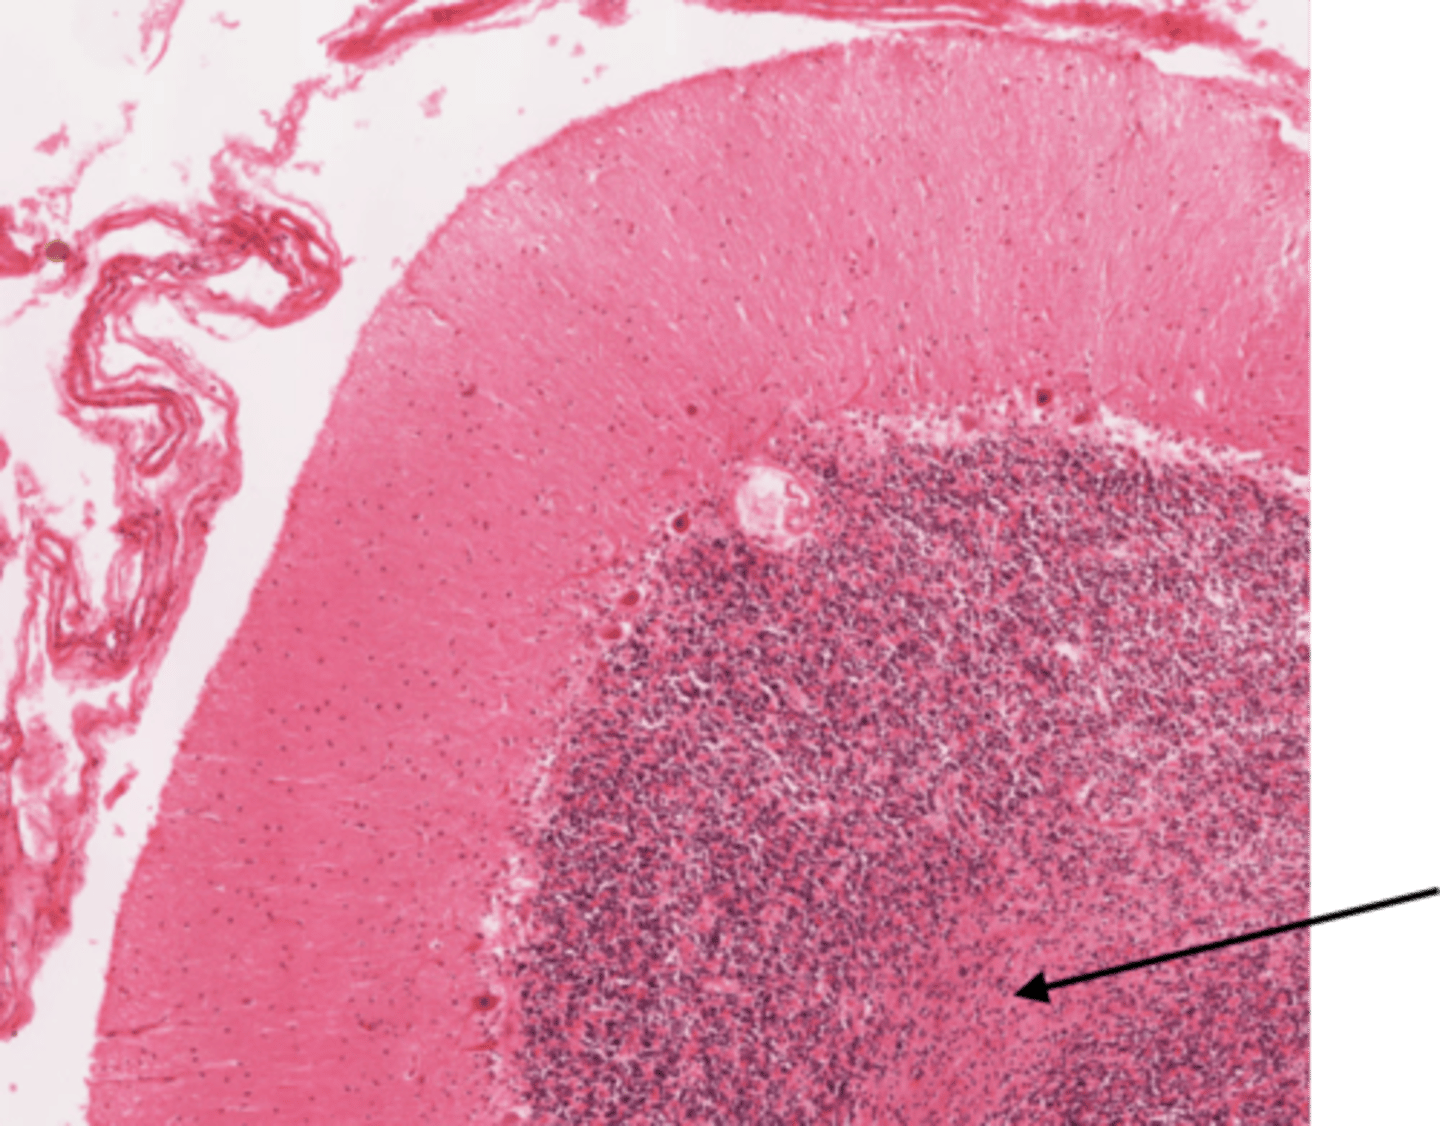

Identify the part of the spinal cord

dorsal funiculi

lateral funiculi

ventral funiculi

dorsal horn

ventral horn

dorsal root of spinal nerve

ventral root of spinal nerve

What is the midline structure that separates the dorsal left and right halves of the white matter

dorsal median septum

What is the midline structure that separates the ventral left and right halves of the white matter

ventral median sulcus

Identify the section of the spinal cord that contains nuclei

gray matter

Identify the section of the spinal cord that contains nerve tracts

white matter

central canal